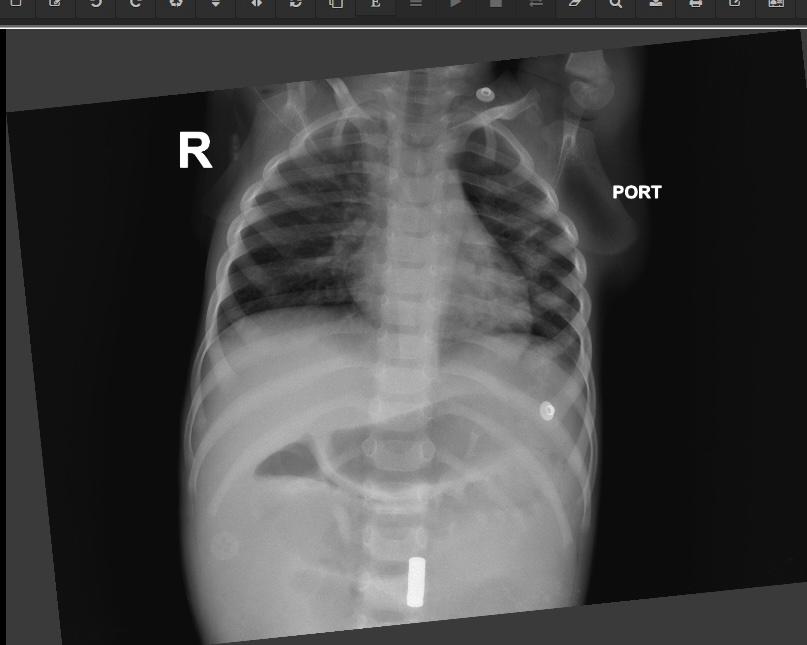

“The three-year-old boy, Pragyan, was brought in with violent abdominal pain and continuous vomiting. Scans showed multiple foreign objects lodged in his intestines. During surgery, doctors found ten magnets had clamped together inside, tearing holes at eight different points and destroying the shortest section of the small intestine, called the duodenum. Barely 24 hours later, his four-year-old sister, Hitanshi, arrived at the hospital with similar symptoms. Investigations revealed six magnets inside her stomach, which had caused multiple perforations and tissue death in her stomach cavity,” said the hospital.

Since small magnets can scatter to different sections of the stomach and intestines, the team used a C-Arm fluoroscopy machine, which provides real-time X-ray imaging during the operation to ensure precision. The careful combination of intricate repair and advanced imaging was crucial to securing children’s survival within 48 hours.